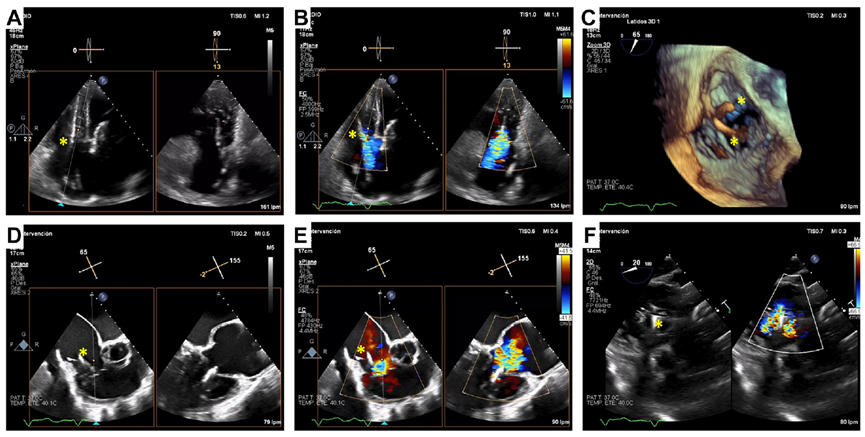

術后經食道超聲,僅微量瓣周漏

起搏器/ICD導線引起的TR是三尖瓣反流的主要機制,這也是三尖瓣介入治療面臨的極大挑戰。既往臨床實踐已證實LuX-Valve系列產品在高危三尖瓣反流患者中的安全性和有效性,并且術后并發癥發生率低。LuX-Valve系列產品瓣膜應用室間隔“錨定區域”作為特殊的錨定機制,保證了瓣膜的穩定性。同時,多種尺寸的、較大的自適應防漏環可有效避免瓣周漏的發生,所以對于術前有起搏器/ICD植入史的患者,LuX-Valve系列產品可以最大程度減少由導線引起的三尖瓣殘余反流。本文報道的病例有兩根導線,其中一根材質較厚,位置在瓣膜的中心,手術的結果依然很完美。尤其是,LuX-Valve系列產品經導管三尖瓣置換系統的調整和釋放是在緩慢而完全受控的情況下進行的,術者可精確定位和控制導線的位置。隨訪期間,LuX-Valve Plus瓣膜沒有出現衰敗或血栓的現象,患者生活質量也大為改善。